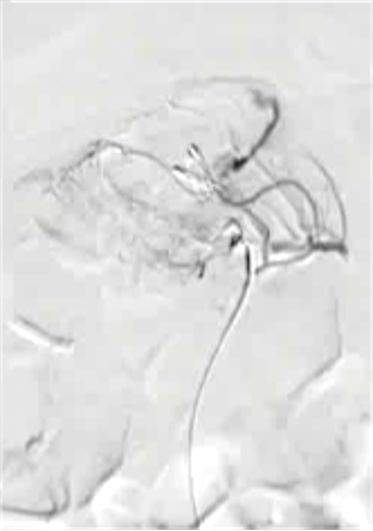

病例1 70/40 mmHg

病例1 20μg Arterenol (去甲肾上腺素) 155/85mmHg

|

激发下 |

栓塞后 |